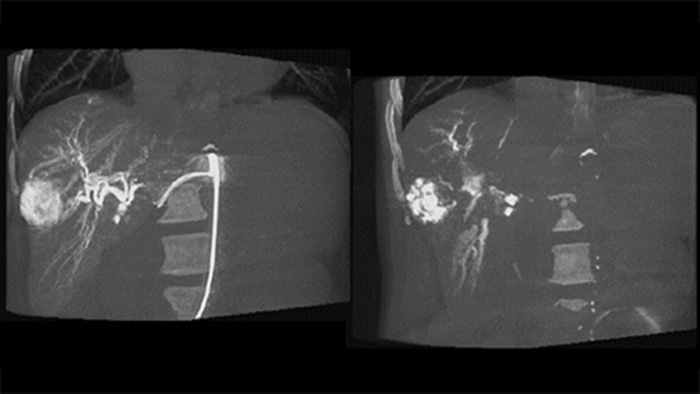

Al abrir el arco a la izquierda del paciente, CBCT Open permite el posicionamiento fuera del centro de la mesa del paciente y, por lo tanto, un mejor centrado del FOV3-4.Esto aumenta significativamente la cobertura de imágenes para ayudar a visualizar los tumores en la periferia del hígado.4.

CBCT Dual permite la adquisición 3D de una fase arterial para visualizar estructuras vasculares y una post-arterial (fase retardada) para visualizar la acumulación de medio de contraste, en un solo paso automático5.